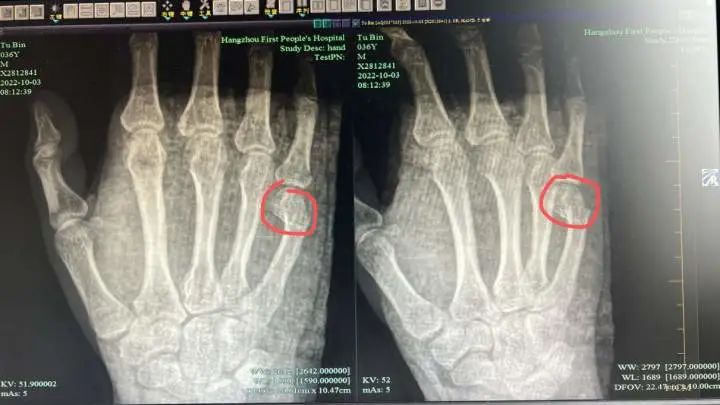

杭州的一位父亲

因在辅导孩子写作业时

没控制住脾气

一气之下用手怒锤桌子

结果把自己送进医院……